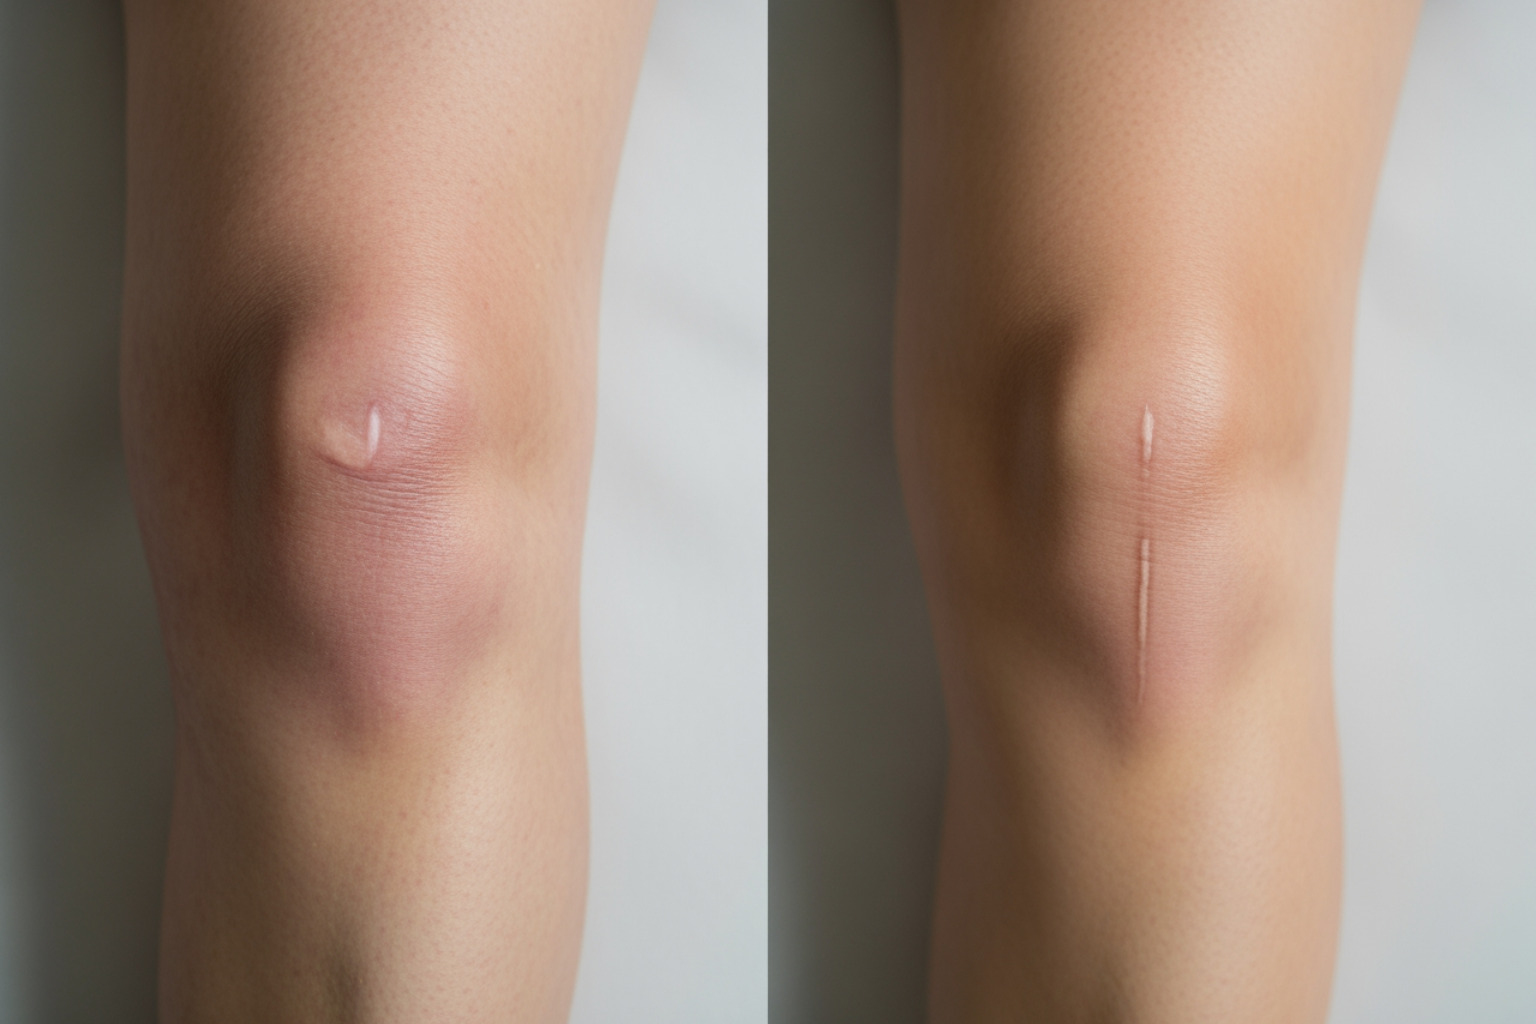

Knee arthritis symptoms tend to develop gradually. Pain is often the first sign, worsening with activity. Other common symptoms include:

- Swelling due to inflammation inside the joint.

- Arthroscopy: A surgeon uses a tiny camera and small incisions to remove loose cartilage or bone fragments (debridement) or repair a torn meniscus. However, for general osteoarthritis, research shows that simply cleaning out the joint has limited long-term benefit.

- Partial knee replacement: If damage is confined to one compartment of the knee, a surgeon can replace only that damaged section. This procedure often leads to a faster recovery and a more natural feeling knee. You can learn about partial knee replacement surgery to see if it's right for you.

- Total knee replacement: This is the most common procedure, where all damaged joint surfaces are replaced with artificial components made of metal and plastic. The goal is to eliminate bone-on-bone friction and restore movement. Modern replacements are durable, often lasting 15-20 years or more, with over 90% of total knee replacements still functioning well after 15 years.